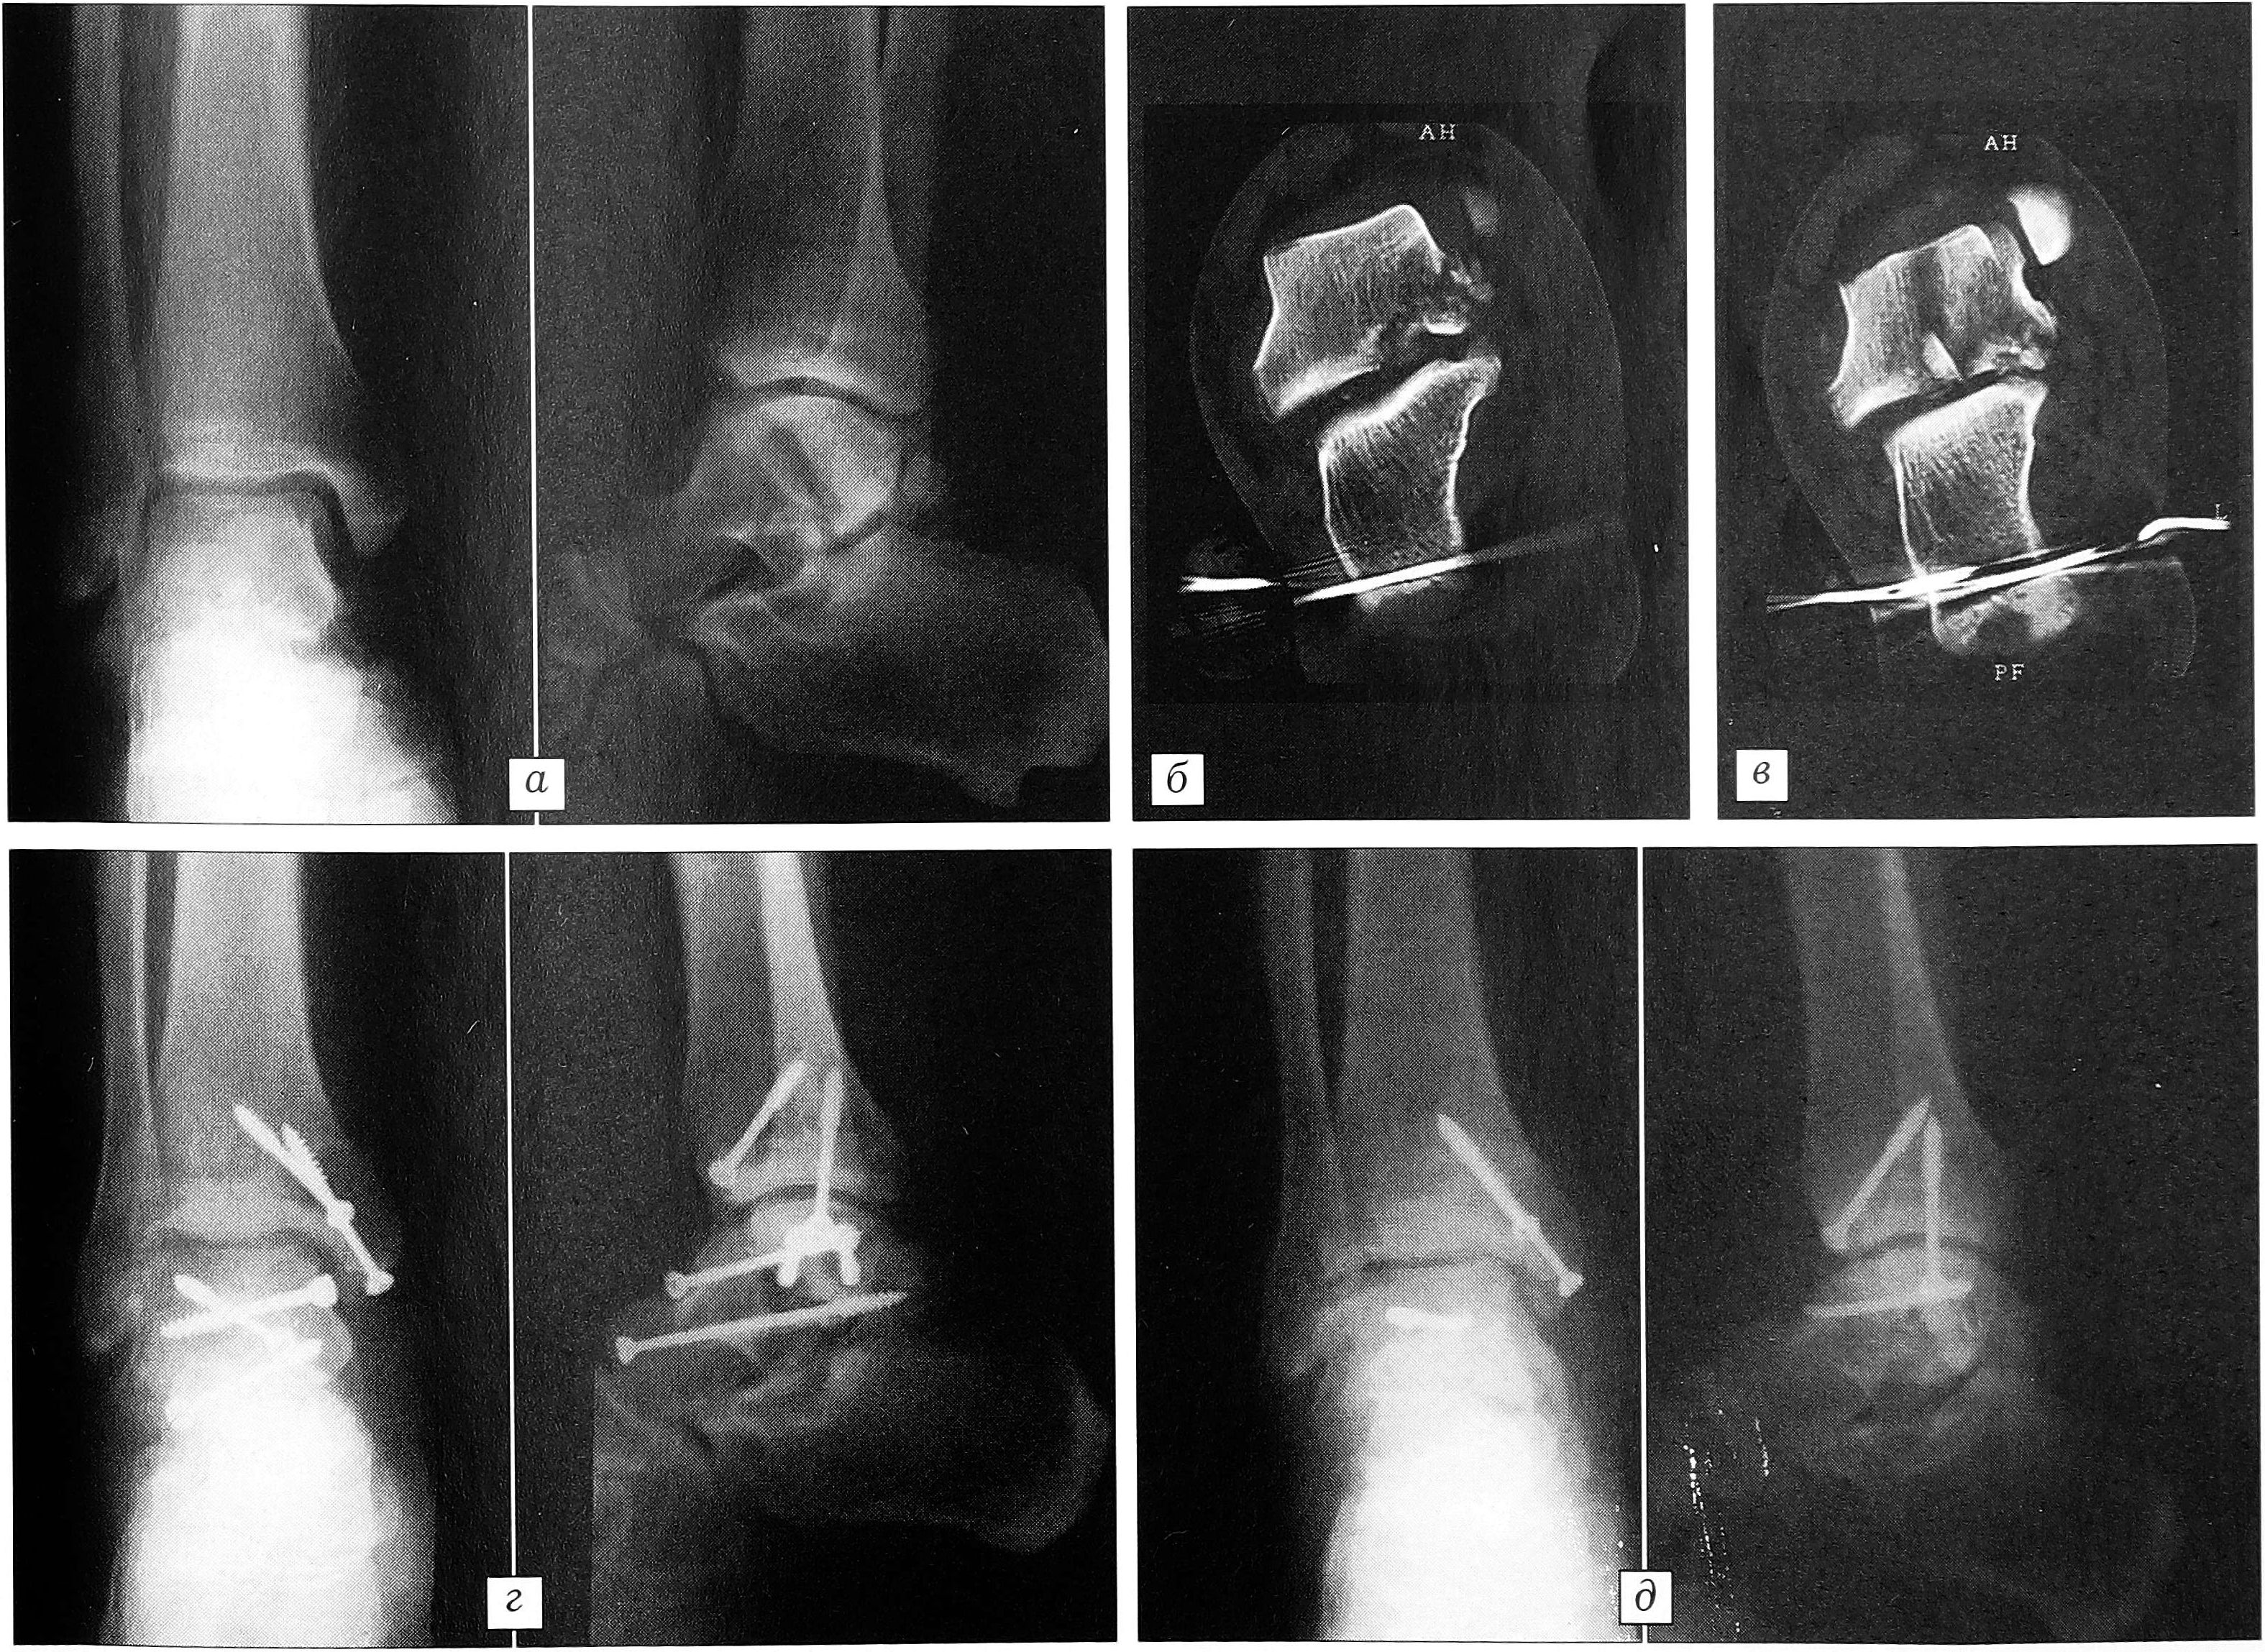

Проанализировав данные литературы [2, 4, 9, 11] и наблюдения из собственной клинической практики, мы сочли целесообразным включить в обследование больных метод компьютерной томографии. Это позволило получить неоценимую информацию, особенно для диагностики переломов тела и блока таранной кости, локализующихся в сагиттальной плоскости, которые при отсутствии значительных смещений не выявляются с помощью рентгенографии в стандартных укладках. КТ была выполнена у 12 (24%) больных, при этом полученные результаты существенно повлияли на дальнейшую тактику.

Пример 1. Больной А., 31 года, получил травму на производстве: оступившись, упал с высоты 1,5 м. Госпитализирован с диагнозом: закрытый перелом блока таранной кости правой стопы (рис. 1, а). Наложена система демпферированного скелетного вытяжения за пяточную кость. Для определения степени и вида разрушения таранной кости, кроме рентгенографии в типичных укладках, произведена компьютерная томография. Диагноз уточнен: закрытый оскольчатый перелом блока и тела таранной кости во фронтальной и сагиттальной плоскостях (рис. 1, б, в). Примечательно, что продольный перелом (в сагиттальной плоскости) на типичных рентгенограммах не выявляется. Больной оперирован на 3-и сутки. Медиальный доступ с отсечением внутренней лодыжки. Выполнен остеосинтез отломков блока таранной кости четырьмя винтами. Внутренняя лодыжка фиксирована двумя винтами (рис. 1, г). Послеоперационное течение без осложнений. Контрольный осмотр через 3 мес после операции: пациент ходит с помощью трости, болей, отеков нет. На контрольных рентгенограммах признаков асептического некроза таранной кости не выявлено. Приступил к труду без ограничений через 4 мес. Винты из таранной кости удалены через 11 мес, один винт при удалении сломался (рис. 1, д).

Рис. 1. Рентгенограммы и компьютерная томограмма больного А. а — рентгенограммы при поступлении; б, в — КТ во фронтальной проекции при поступлении: б — многооскольчатый перелом внутреннего края тела таранной кости, в — хорошо виден перелом тела таранной кости, проходящий в сагиттальной плоскости, с интерпозицией мелких костных осколков; г — рентгенограммы после открытой репозиции и фиксации таранной кости четырьмя винтами; д — рентгенограммы при удалении металлоконструкций: в блоке таранной кости виден сломавшийся винт, внутренняя лодыжка фиксирована вновь.